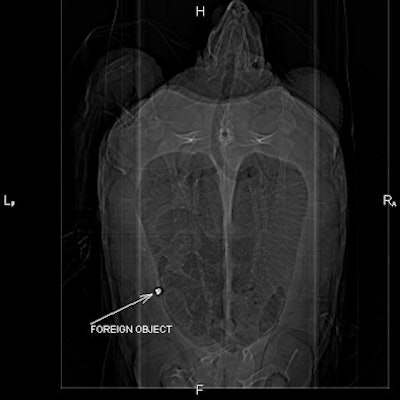

A CT scan of the pelvis and abdomen of Hemingway, a hawksbill sea turtle with an indiscriminate appetite, showed bolts from the aquarium's Tortuga Cay exhibit and an abscess in her intestines, according to a statement from the imaging provider.

"We actually saw bolts from the exhibit inside her," Texas State Aquarium dive officer and senior aquarist Deanna Gallier said. "She took a big bite out of the exhibit."

| CT scan of Hemingway's pelvis and abdomen revealed aquarium exhibit bolts and an abscess in her intestines. The bolts were successfully removed. |